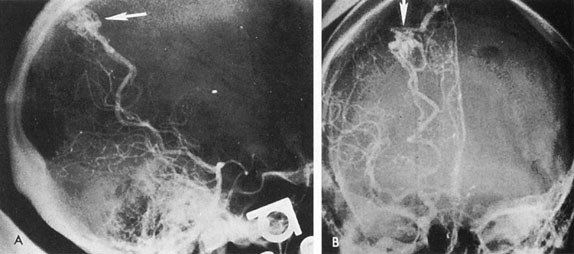

Therapy for carotid–cavernous fistula is directed toward relieving ocular symptoms, especially where visual loss is threatened, with the goal being thrombosis of the fistula with normalization of orbital hemodynamics. Various arterial ligatures, trapping procedures, controlled embolizations, and even direct intracranial attacks have been advocated, but the current trend indicates the great advance represented by intravascular closure using detachable balloon microcatheterization techniques (Fig. 17).106 Complications of these techniques include transient or fixed hemispheral dysfunction, cranial nerve palsies, field loss, and pseudoaneurysm formation.106,112 At least one case of acute angle-closure glaucoma was reported after transvenous embolization of a traumatic carotid–cavernous fistula necessitating emergency laser iridotomy.113 The complication was thought to arise from oculomotor palsy related to the coil pack within the ipsilateral cavernous sinus. However, complication rates are apparently low. In a series of 100 consecutive patients treated for direct carotid–cavernous fistula with detachable balloons, Lewis et al 114 reported an approximately 4% overall complication rate. Endovascular treatment of dural (indirect) carotid–cavernous fistulae is usually directed transvenously also using fibered platinum coils or, less often, liquid adhesive. A recent retrospective evaluation of 135 consecutive patients treated for dural carotidcavernous fistulae over a 15 year period by Meyers et al115 revealed low permanent morbidity of 2.3% and high 90% rate of clinical cure.

Fig. 17. A 32-year-old woman was accidentally shot in the right eye with a low-velocity missile. The initial recovery was excellent, except for loss of the right eye. Five days after the injury, left proptosis and bruit developed. Two weeks after the injury, she developed paralysis of the left sixth and fourth nerves, and visual acuity decreased to 20/400 (6/120) in her remaining (left) eye. An interventional neuroradiologic procedure was performed with complete return of function in the left eye. A: Left carotid arteriogram with immediate opacification of entire cavernous sinus (arrows). B: One-half second after (A) there was extensive filling of dural venous channels and orbital veins. C: Detachable flow-guided balloon (arrows) placed in the fistula under fluoroscopic control and opacified with contrast medium. D: Follow-up left carotid arteriogram after balloon (arrows) placement. The fistula was completely closed with preservation of carotid flow. (Courtesy of Dr. Charles Kerber.)